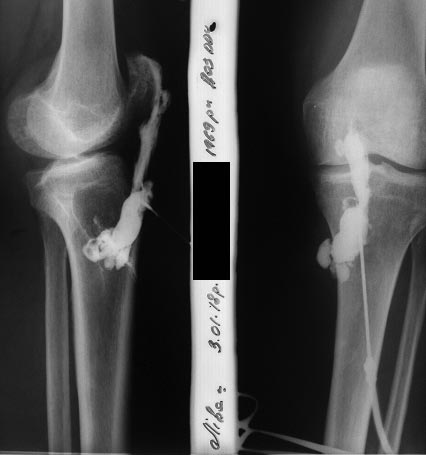

Добрый день. Вот фотографии коленного сустава. На догоспитальном этапе абсцесс самораскрылся через область п/о рубца, сделана через этот дефект мягких тканей фистулография.

фистулография